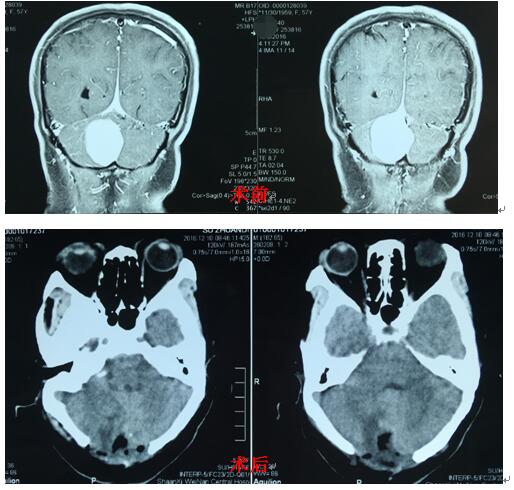

患者苏某,女,52岁,渭南临渭区人, 于数月前行CT检查时发现小脑占位,曾在省内多家医院就诊咨询,经反复考虑后,入住我院神经外科二病区。入院后行颅脑MR平扫及增强提示:小脑镰旁脑膜瘤。我市神经外科首席专家白西民主任医师高度重视,积极进行术前准备,在冯毅副主任医师及朱奕儒住院医师的配合下行小脑镰旁脑膜瘤切除术,术中全切肿瘤,手术顺利。术后病理报告为纤维细胞型脑膜瘤。该患者术后恢复良好,无神经功能障碍。

脑膜瘤虽为良性肿瘤,患者预后较好,但由于此患者肿瘤位于小脑镰旁,紧邻右侧横窦及窦汇,手术难度较大。因此,手术者必须有扎实的神经外科解剖知识、熟练的显微外科技术。本例手术在神经外科二病区医务人员的努力下成功切除肿瘤,使我院在小脑肿瘤的治疗上提高到一个新的高度。